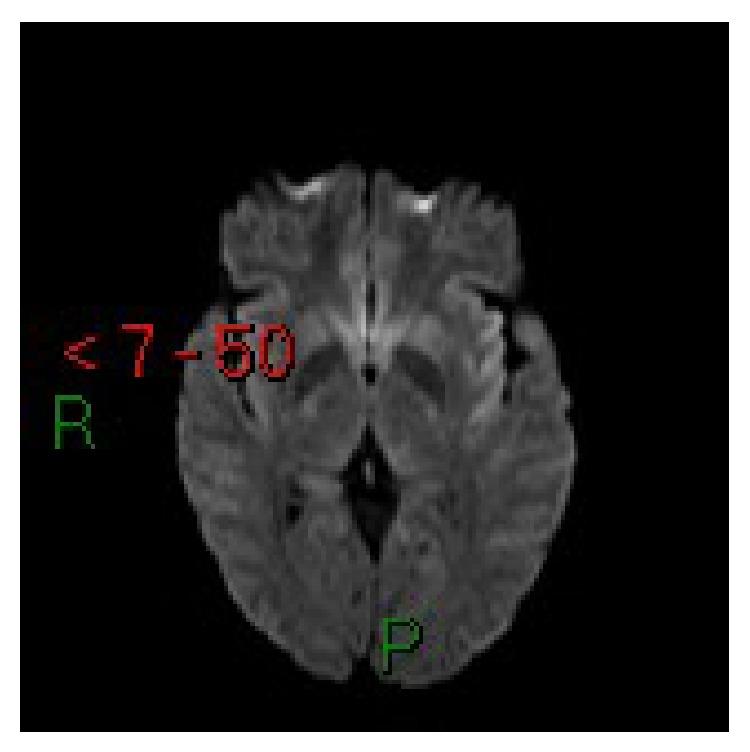

Posterior reversible encephalopathy syndrome (PRES) is a neurological syndrome associated with a number of conditions including preeclampsia. It is characterized by seizures, alteration of consciousness, visual disturbances, and symmetric white matter abnormalities, typically in the posterior parietooccipital regions of the cerebral hemispheres, at computed tomography (CT) and magnetic resonance (MRI). We report three new cases of PRES in preeclamptic patients and describe the management of these patients. We present a brief review of other cases in the literature, with particular attention to the anesthetic management.

后部可逆性脑病综合征(PRES)是一种与包括先兆子痫在内的多种病症相关的神经综合征。其特征为癫痫发作、意识改变、视觉障碍以及对称的白质异常,在计算机断层扫描(CT)和磁共振成像(MRI)上,这些异常通常出现在大脑半球的后顶枕叶区域。我们报告了3例先兆子痫患者发生PRES的新病例,并描述了这些患者的治疗情况。我们对文献中的其他病例进行了简要综述,尤其关注麻醉管理。